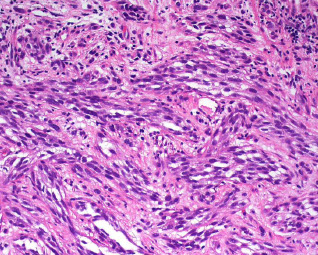

Piloleiomyoma

Multiple firm red-brown lesion in 3rd decade that are derived from arrector pili muscle and can be painful when exposed to cold

Reed's syndrome - AD fumarate hydratase gene mutation; may be related to papillary RCC or uterine leiomyomas if multiple

Micro: Pilo arrector muscle on roids c interlacing sm muscle and cigar-shaped nuclei and perinuclear vacuole

- circumscribed but non-encapsulated nodule